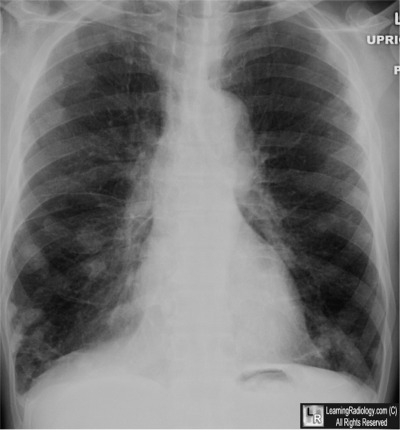

Frontal Chest Radiograph

What is the most likely diagnosis?

- 63 year-old male with history of arthritis